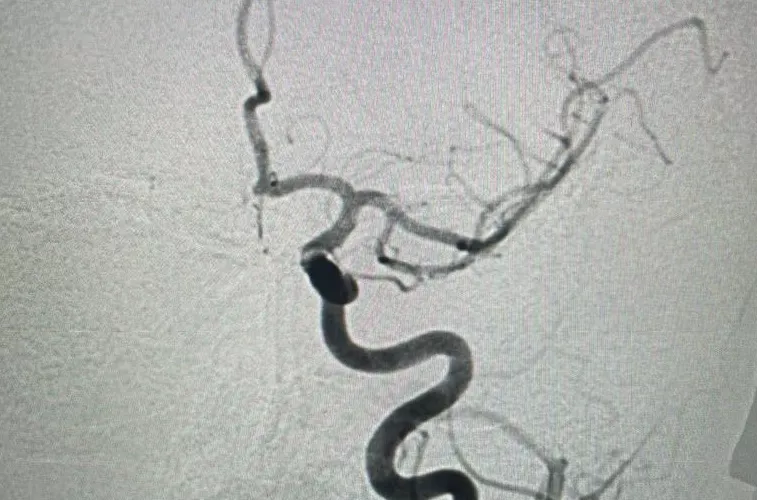

После обследований, в том числе КТ, у пациентки диагностировали ишемический инсульт в бассейне левой внутренней сонной артерии. Крупный тромб нарушил кровоснабжение головного мозга.

- Пациентку доставили в операционную, где команда специалистов - рентгенэндоваскулярный хирург Георгий Корелов, ассистент Эльдар Афаунов, операционная сестра Лариса Яшина и анестезиолог-реаниматолог Оксана Казанкова - выполнили ювелирную по точности операцию. При помощи специальных катетеров врачи через небольшой прокол артерии нашли проблемное место и с помощью вакуума извлекли тромб из внутренней сонной артерии, - рассказали «Кубанским новостям» в пресс-службе больницы.